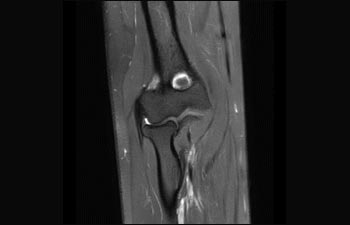

La Sra. Silvia Schiffer, directora y radióloga experta en la clínica Radiologie Schiffer, en Alemania, comparte sus experiencias con el sistema de RM Prodiva 1.5T.

Conozca la opinión de los primeros usuarios de Ingenia Prodiva 1.5T acerca de sus experiencias con el sistema y cómo influye este en su centro de diagnóstico por imagen.